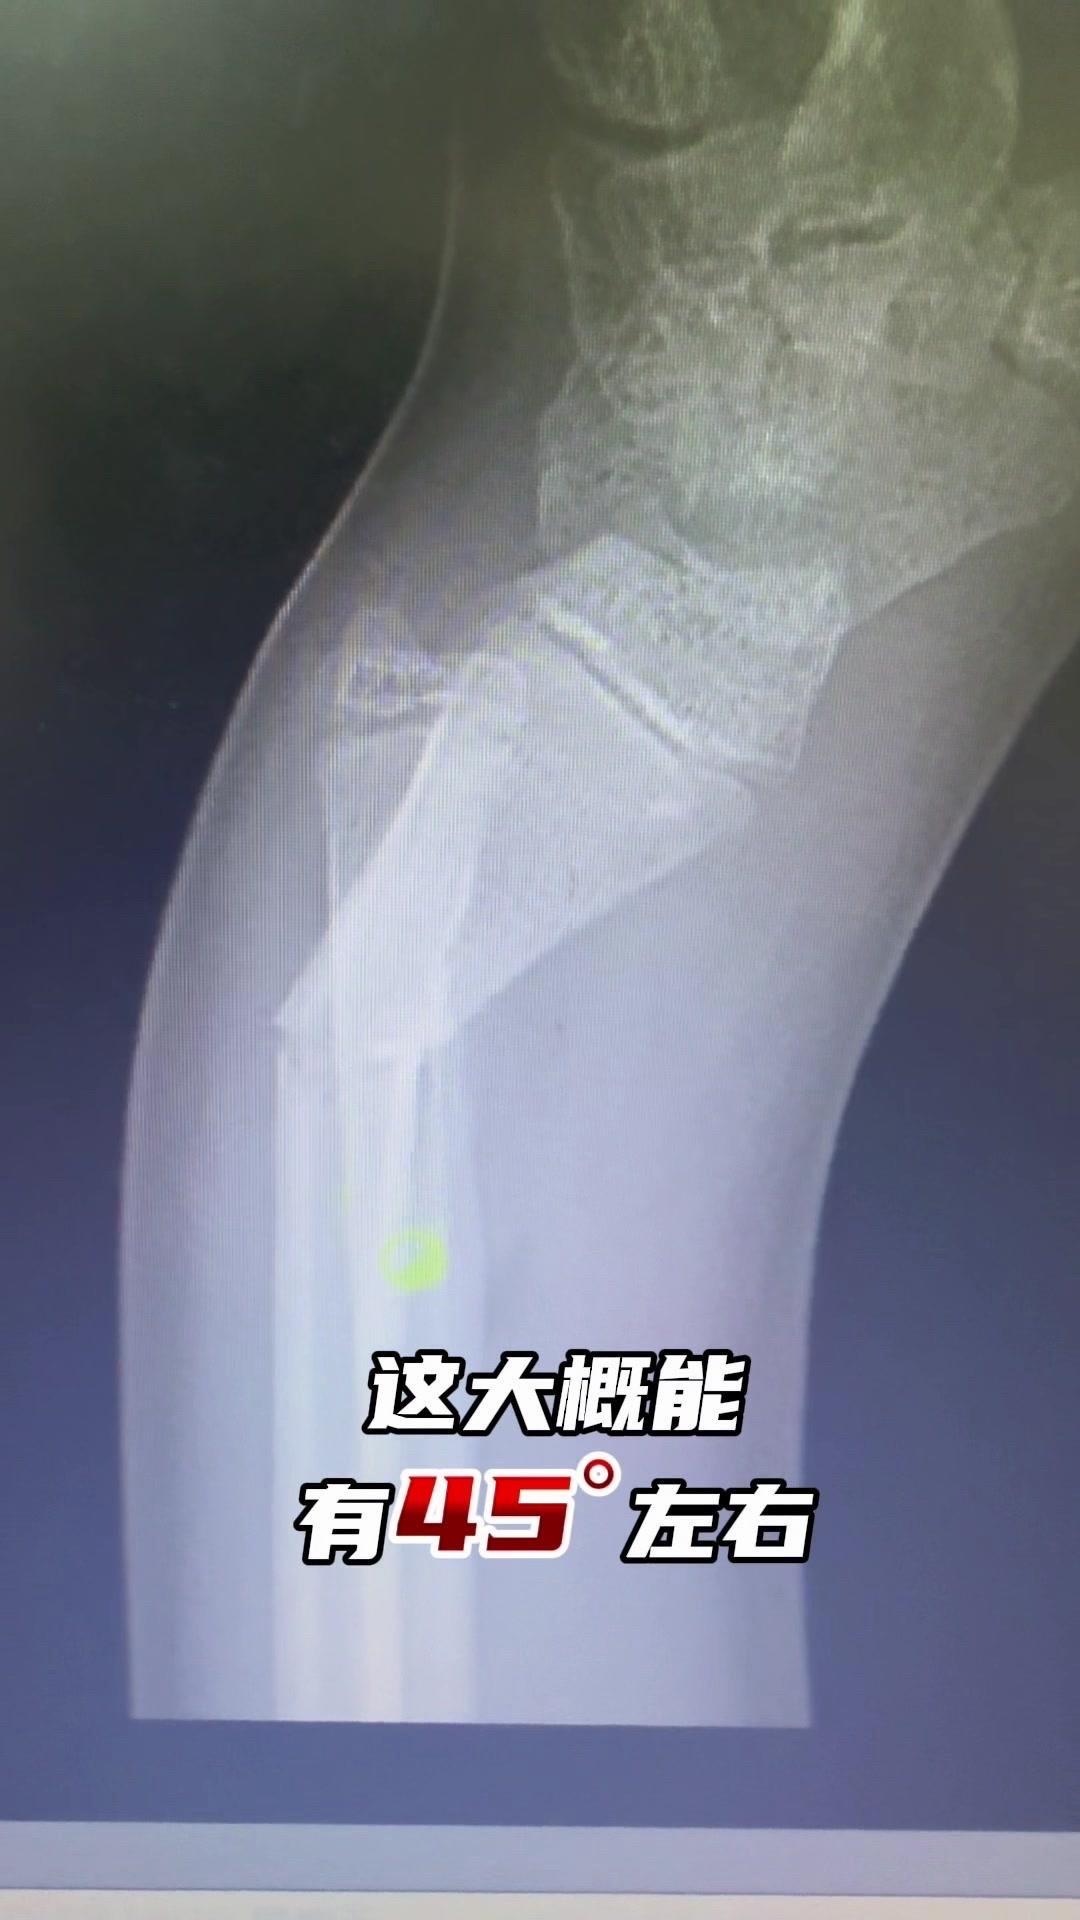

儿童骨折别拖延!💡上周接诊一个10岁女孩,摔了一跤后腕部疼痛还伴有畸形,家长觉得是小伤没在意,结果一周后孩子疼得更厉害,畸形也更明显了。来医院拍片一看,妥妥的骨折,而且才一周就开始出现模糊骨痂,掌区还有45度左右的成角畸形。家长这才意识到问题严重性,其实孩子受伤后出现疼痛、畸形,哪怕看起来不严重,也得及时检查,别让小问题拖成大麻烦。